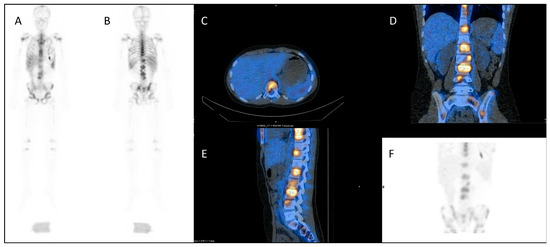

The use of PSMA (prostate-specific membrane antigen) targeted radiopharmaceuticals overcomes this, offering a more personalised treatment, targeting as it does the PSMA receptor on the cell surface of prostate cancer cells directly. Prostate-specific membrane antigen is a 750 amino acid type II transmembrane glycoprotein. It is expressed by most epithelial cells, but over-expressed (up to 1000-fold) by the majority of prostate cancer cells. Diagnostic PET imaging with 68Ga PSMA exploits the internalisation undergone by the receptor, allowing radioisotopes to be concentrated within the cell, having bound to the external component of the PSMA (Figure 2A,B). Uptake is also seen in the salivary glands, kidney and proximal small intestine. There is a correlation between the higher Gleason score of prostate cancers, castrate-resistance and PSMA expression, making the PSMA receptor an optimal target for theragnostic development [31].

Figure 2.

A PMSA-based theragnostic approach to metastatic prostate cancer. (A) Anterior view of maximum intensity projection, and (B) axial view of 68Ga-PMSA PET CT (positron emission tomography, computed tomography) demonstrating left posterior rib metastasis. Then, following 177Lu PMSA administration, (C) anterior view planar scintigraphy and (D) SPECT CT (single photon emission computed tomography, computed tomography) imaging. While these show similar appearances, post-therapy imaging has a lower resolution as the techniques are different.

The PSMA-based radiopharmaceuticals developed for therapy include 1311, 90Y and 177Lu. The side effects of all forms of PSMA-based radiopharmaceutical included dose to salivary glands and kidneys. 177Lu is a beta-emitter, with a shorter range than 90Y (1.5 mm 177Lu; 12 mm 90Y), giving it a more desirable side-effect profile. There is a good correlation between 68Ga PSMA and 177Lu PSMA distribution, allowing for pre-therapeutic dosimetric calculation to be performed in order to minimise toxicity (Figure 2C,D) [32]. 177Lu emits co-incident gamma emission, allowing post-therapeutic imaging to both confirm uptake, and allowing dosimetric calculation for subsequent therapeutic administrations [33]. 177Lu DOTA-PSMA-617 is the most extensively investigated radiopharmaceutical of this class, with its efficacy demonstrated in phase II randomised trials which showed a biochemical response in two thirds of patients. Phase III trials—TheraP and VISION—are currently underway, with completion expected in 2021 [34,35].